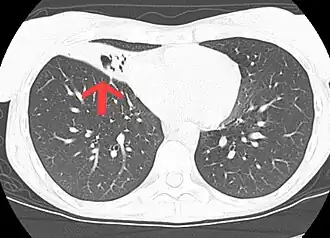

L'infection à Mycobacterium avium-intracellulare est un type d'infection à mycobactéries non tuberculeuses[2]. Plusieurs zones du corps peuvent être touchées, mais les poumons sont le plus souvent touchés[2].

Le diagnostic repose sur les symptômes, la culture des expectorations et l’imagerie médicale[3].